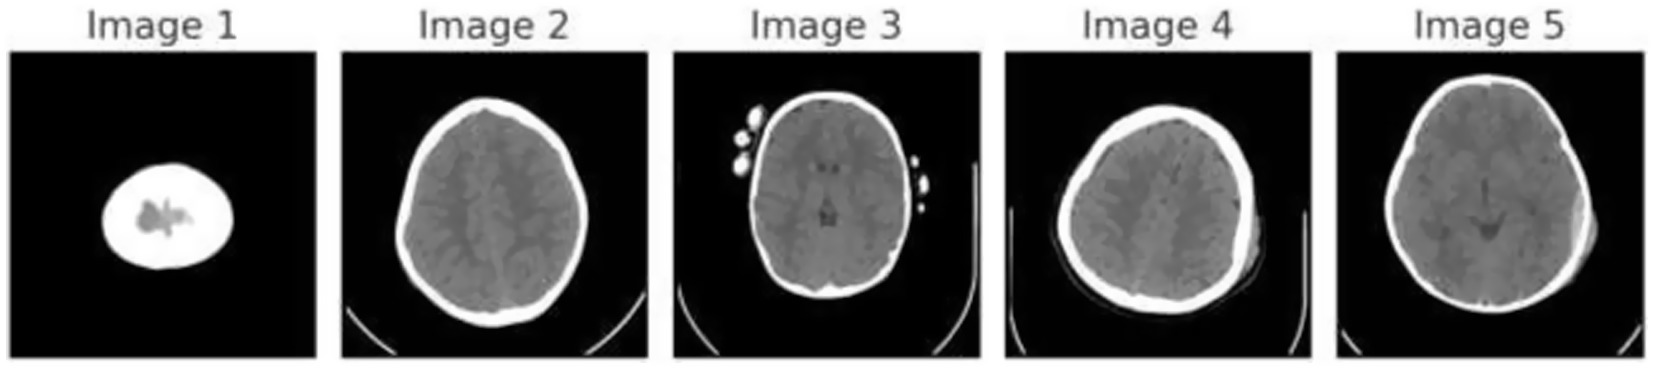

Figure 1 demonstrates the unprocessed and processed CT scan brain scans. Raw images are initially scanned, whereas the processed ones have undergone a procedure of removing noise and normalization to facilitate analysis. Figure 2 shows grayscale, equalized, and edge-detected images of the preprocessed brain images. Gray levels eliminate color, equalization increases contrast, and edge detection emphasizes boundaries of key structures. The CT scan cross-sections shown in Figure 3 are used to obtain details about brain structure and the parts prone to abnormalities such as strokes and tumors. Figure 4 shows different CT scan cross-sections with varying types of stroke, and how ischemic and hemorrhagic strokes can be represented in the brain in a cross-section.

Figure 2

Preprocessed brain images: grayscale, equalized, and edge-detected versions.